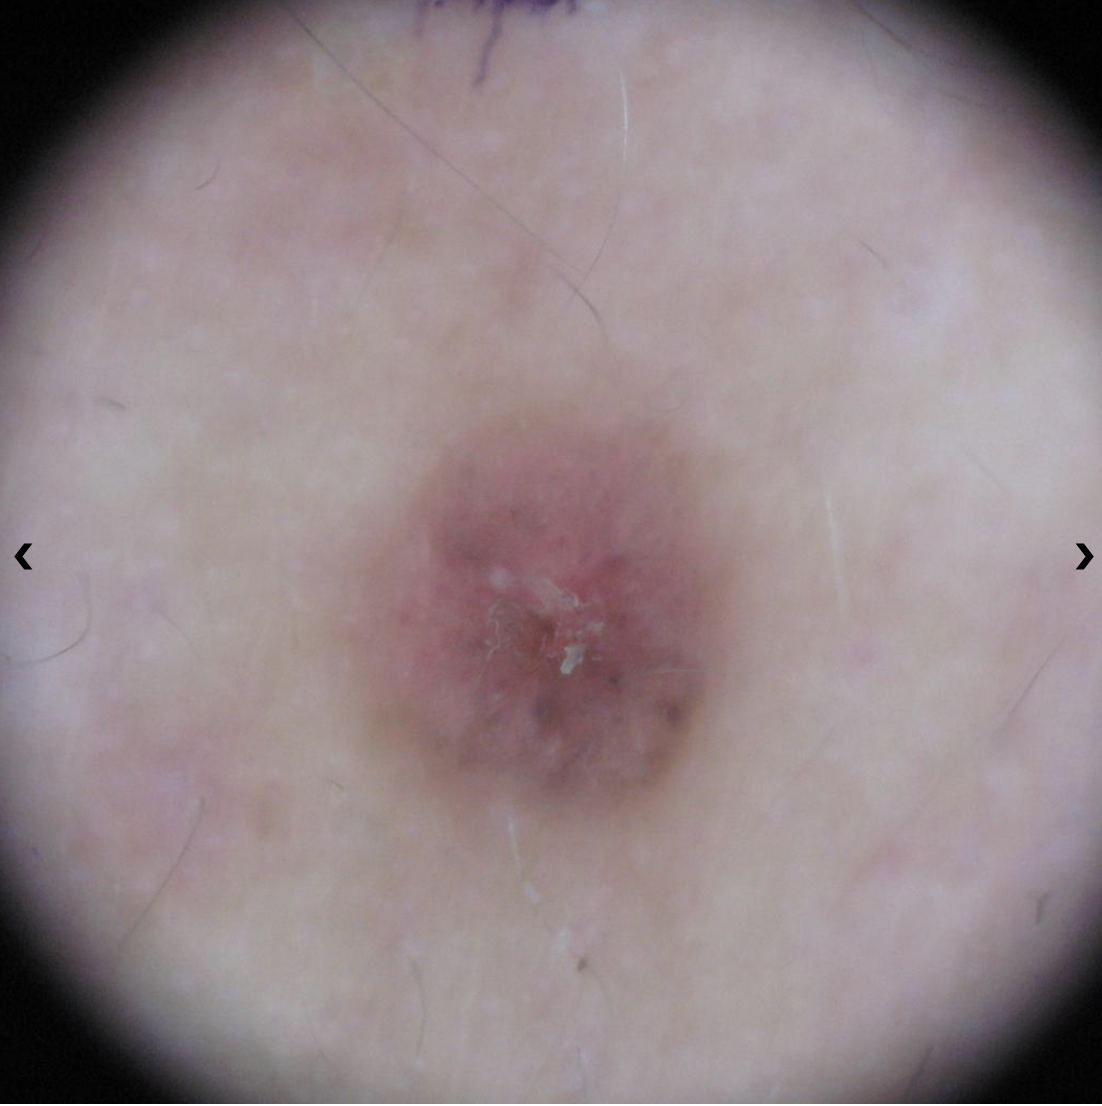

Basal cell carcinoma presenting as a pink growth. Photo: International Skin Imaging Collaboration at isic-archive.com

A small pink growth with a slightly raised, rolled edge and a crusted indentation in the center. (BCC)